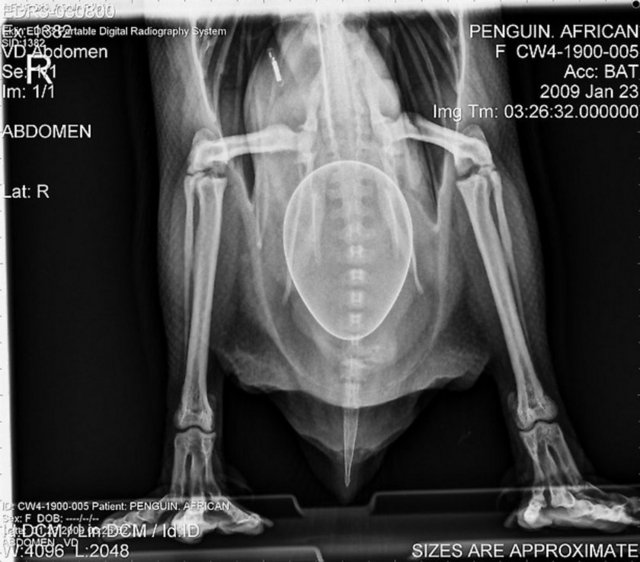

"Özellikle havaalanlarındaki girişlerde iki tür cihazı da görebiliriz. Eşyaların geçirildiği X-Ray cihazında X ışınları kullanılarak görüntüleme yapılır. Çantaların içinde ne olduğu X ışınları ile görüntülenir. Burada uygulanan X ışınlarının eşyalara bir zararı yoktur, birikmez, eşyalarda radyasyon kirliliği yapmaz. Bu cihazların çevresi X ışınlarının insanlara zarar vermemesi için kurşun paravanlarla kaplıdır."